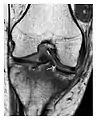

a

b

c

Figure 8: Proximal diaphyseal fatigue fracture of the tibia in a 20-year-old man with a history of regular jogging. (a) Lateral radiograph shows no obvious fracture lines but a subtle localized medial tibial cortex periosteal reaction (arrows). (b) Sagittal reformatted CT image acquired 1-month after the radiograph shows a linear hypoattenuation in the tibial cortex (arrowhead), as well as obvious periosteal thickening (arrows). (c) Sagittal T2-weighted fat-saturated image acquired the same day shows an area of hyperintensity spreading over the proximal tibia (arrows), which is consistent with the presence of proximal tibial fracture.[1]